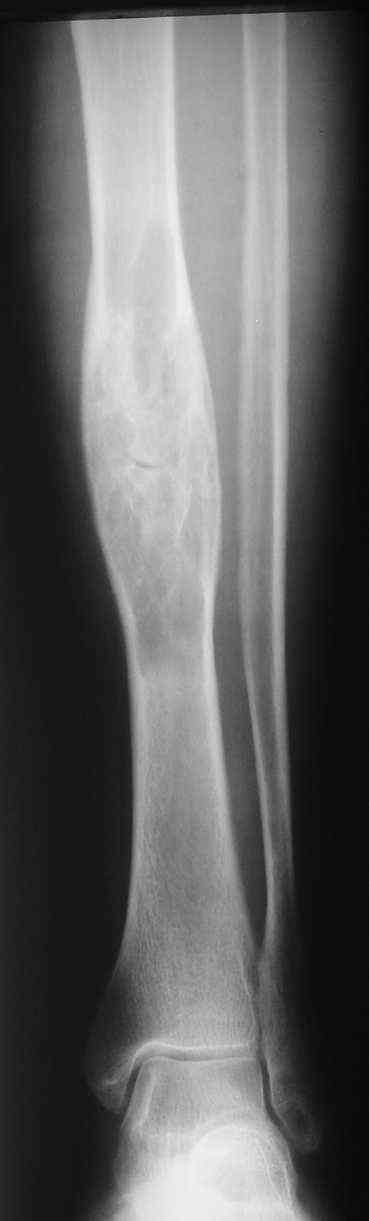

Я поддерживаю мнение доктора Odessky Jacob, что это образоавние возможно фиброзная дисплазия. Случай из моей практики - смотри рентгенснимки во вложении. Правда у моего пациента -полиосальная форма и болезнь проявилась в раннем детстве.

По представленным снимкам наиболее вероятен диагноз "фиброзная дисплазия".

Первоначально нужна трепанбиопсия, чтобы не пропустить другие проблемы, такие как паратиреоидная остеодистрофия, которая также дает очаги в этой области. кроме того и в литературе и на своем опыте могу сказать, что она может рентгенологически имитировать остеокластому. об этом есть работы (JDJS). у нас была пациентка, которая была оперирована 4 раза по поводу остеокластомы разной локализации, но к нам поступила с очагом в б\б кости (примерно как у вашей пациентки). результат трепанбиопсии был остеокластома. и только после операции установлена остеодистрофия. после исследования уровня гормонов обнаружено повышение значительное паратгормона и т.д. после удаления пораженных паращитовидных желез все нормализовалось.